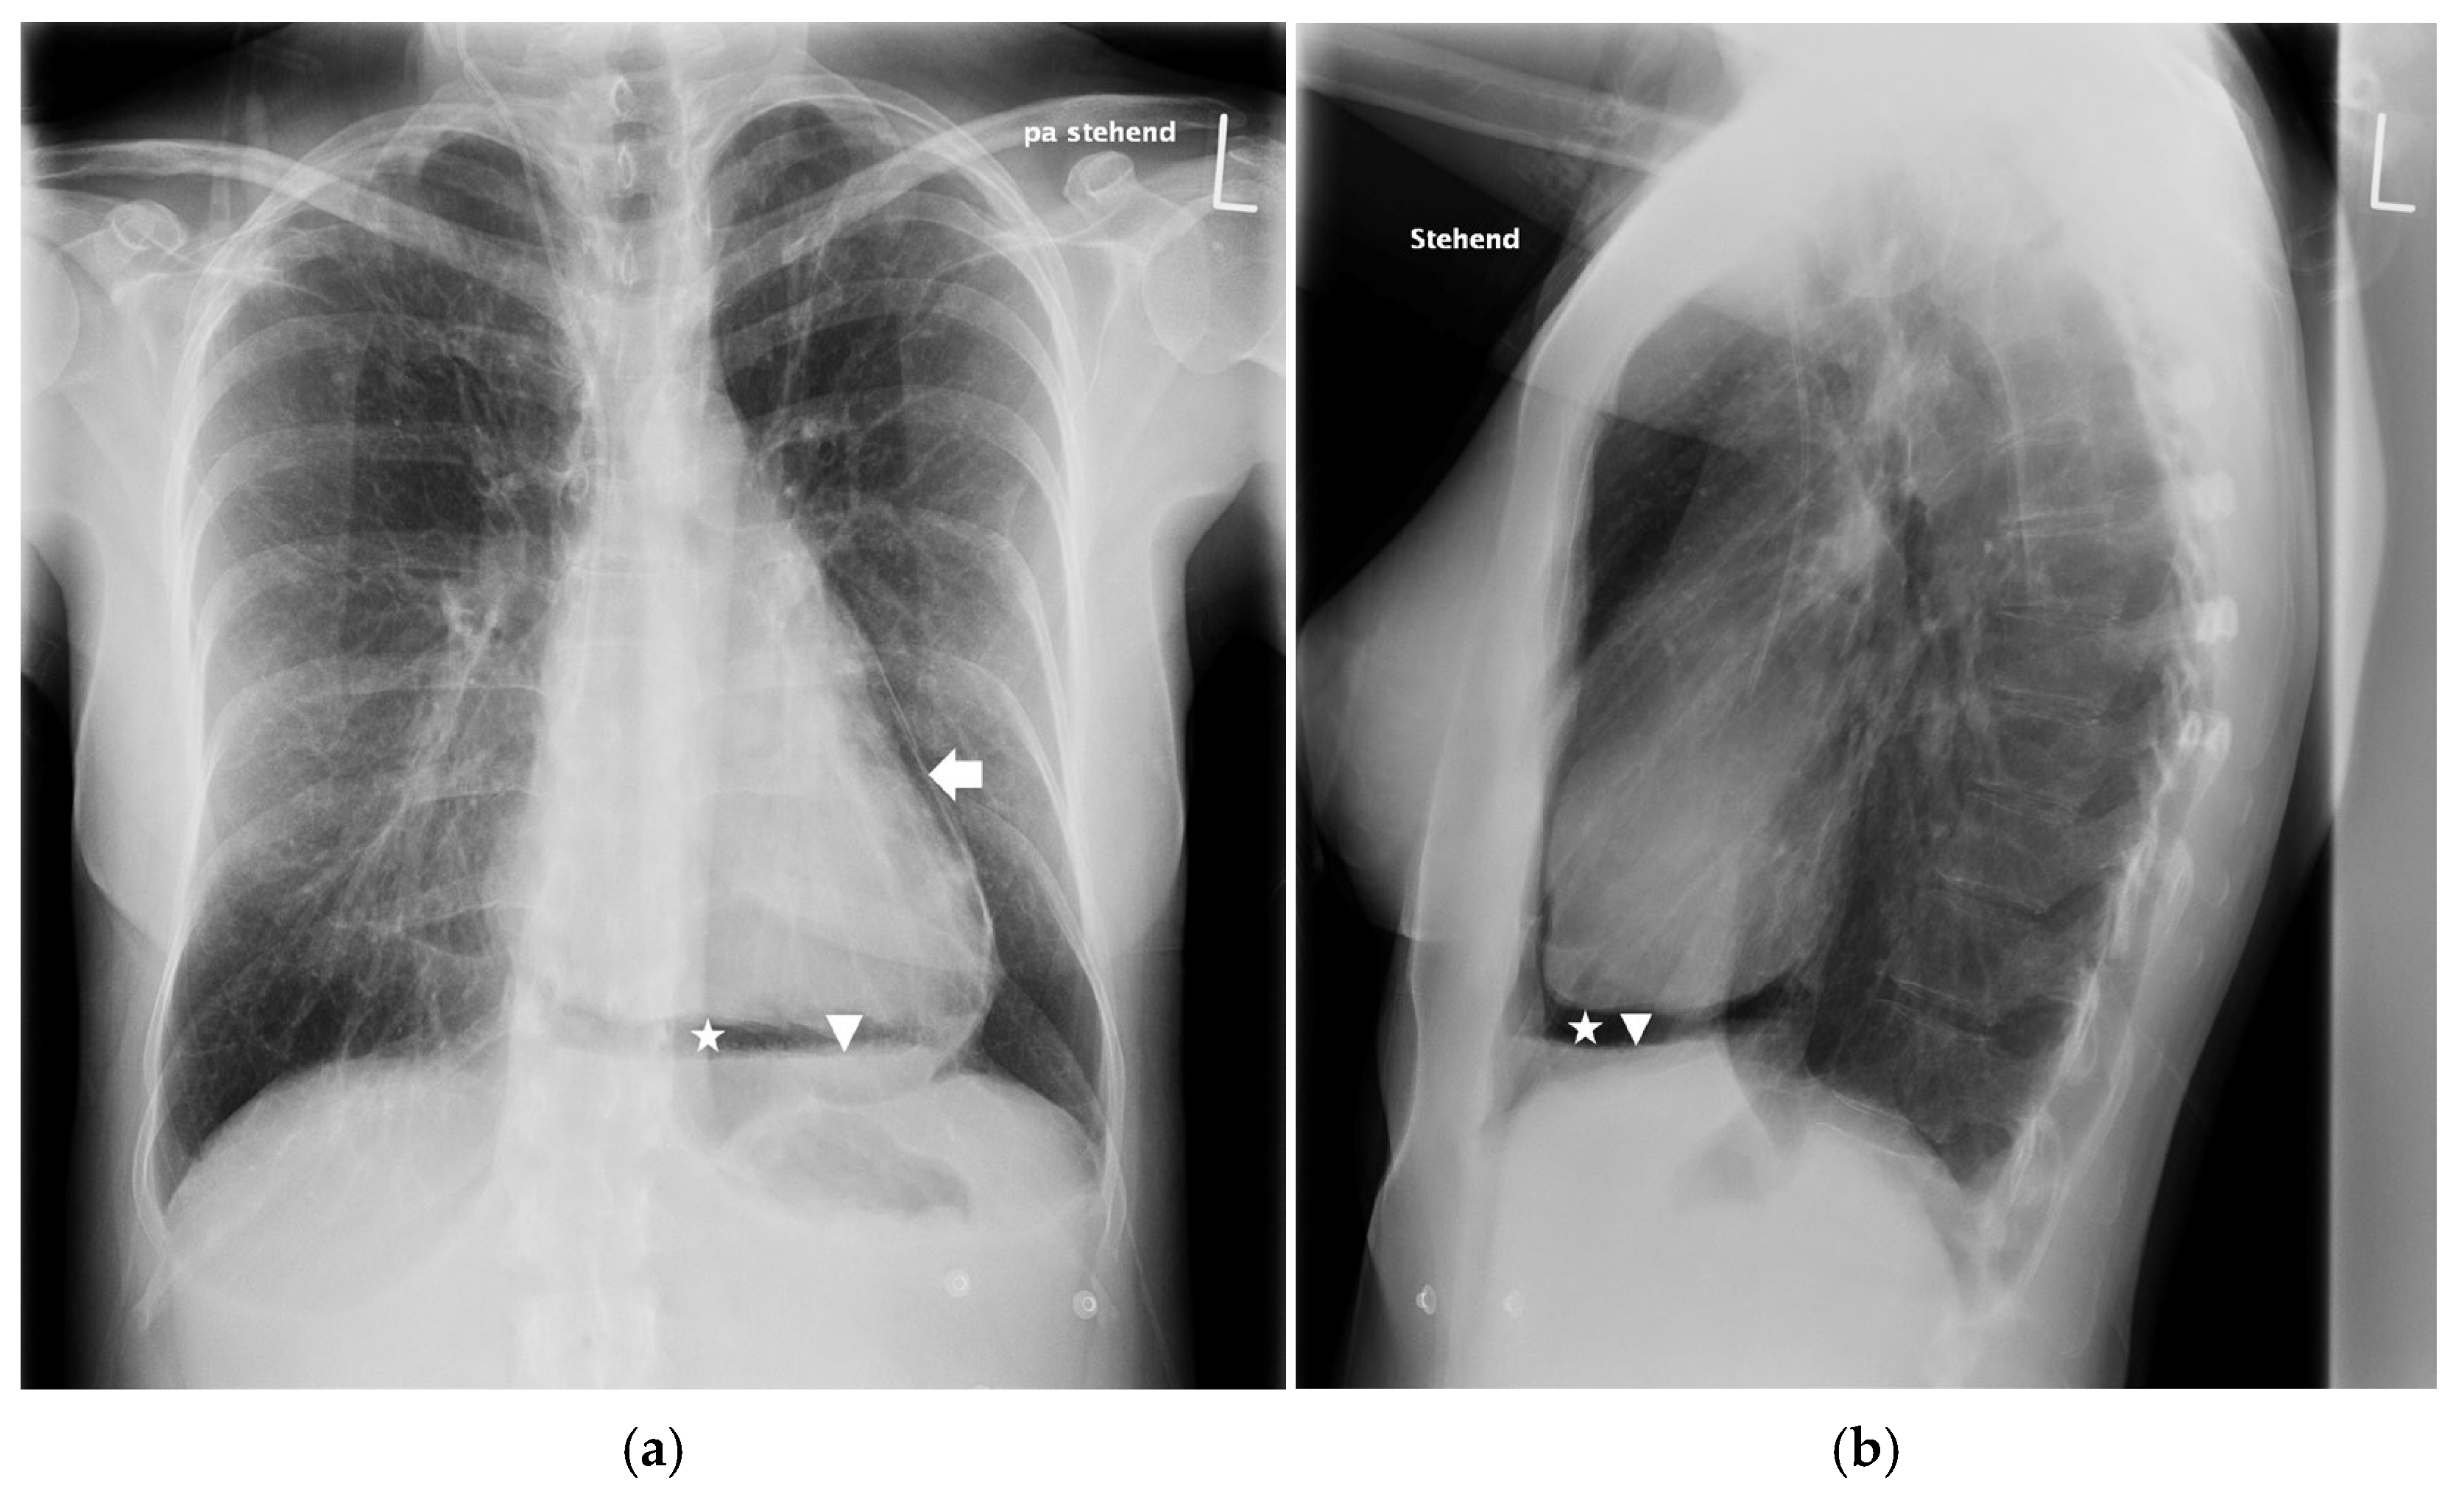

2. Case Report